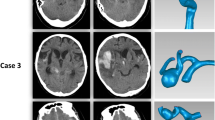

Phenotypic switch and apoptosis of SMCs are favored by oxidative stress and reactive oxygen species (ROS). Using cultured cerebral SMCs, Starke et al. [89] has shown that cigarette smoke exposure increased nicotinamide adenine dinucleotide phosphate oxidase (NOX) 1 expression, favored ROS production, upregulated pro-inflammatory and matrix remodeling genes, and downregulated SMC contractile genes. In a mouse model of IA induced by elastase treatment, they showed that exposure of the mice to cigarette smoke increased the number of IA ruptures, and that the inhibition of NOX1 reduced this incidence of rupture [89]. Finally, the authors showed that IAs from mice in which NOX1 expression or activity was reduced harbored a higher content of SMCs contractile markers. Interestingly, such SMC contractile markers were also reduced in normal arteries of mice exposed to cigarette smoke, while inflammatory and matrix remodeling genes were upregulated [89]. In a cohort of 31 patients with unruptured IAs, we showed that smokers present a lower content of SMCs in their aneurysmal wall compared to non-smokers [55] (Fig. 1). Remarkably, this reduced SMC content is close to the one measured in ruptured IAs. Smoking has been demonstrated to increase MMPs and to reduce collagen synthesis [10], which may result in aneurysmal wall thinning and rupture. Heme oxygenase-1 expression is reduced in smokers [46], which suggests that smoking affects the protective mechanisms against oxidative stress thereby favoring cell death. Moreover, SMC injury and death has also been proposed to be due to the upregulation of calcium channels [26]. Altogether, these studies suggest that smoking favors SMC death and aneurysmal wall degeneration.

Aneurysmal wall of smokers has a lower content in smooth muscle cells in comparison to the wall of non-smokers. Representative images of the wall of four IAs stained with alpha-smooth muscle actin to visualize smooth muscle cells in brown. Human saccular IA samples were obtained during microsurgery by resecting the aneurysmal dome after clipping of the aneurysmal neck. The four IAs coming from the Swiss AneuX biobank were located on the middle cerebral artery of two non-smoker (left images) and two smoker (right images) patients. Scale bar = 100 um